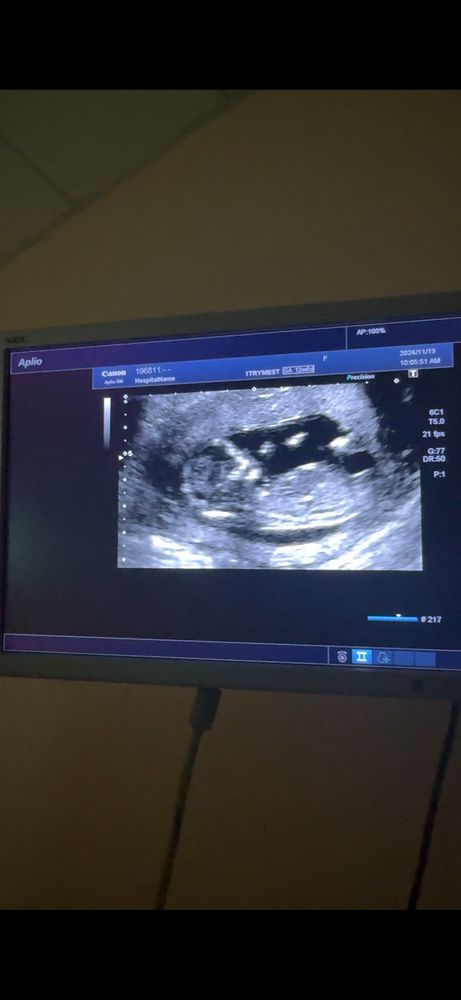

Пол ребенка 1 скрининг

Девочка , угол маленький между спинкой и половым бугорком , почти параллельны. При мальчике большой угол

Девочка, половой бугорок параллельно спинке